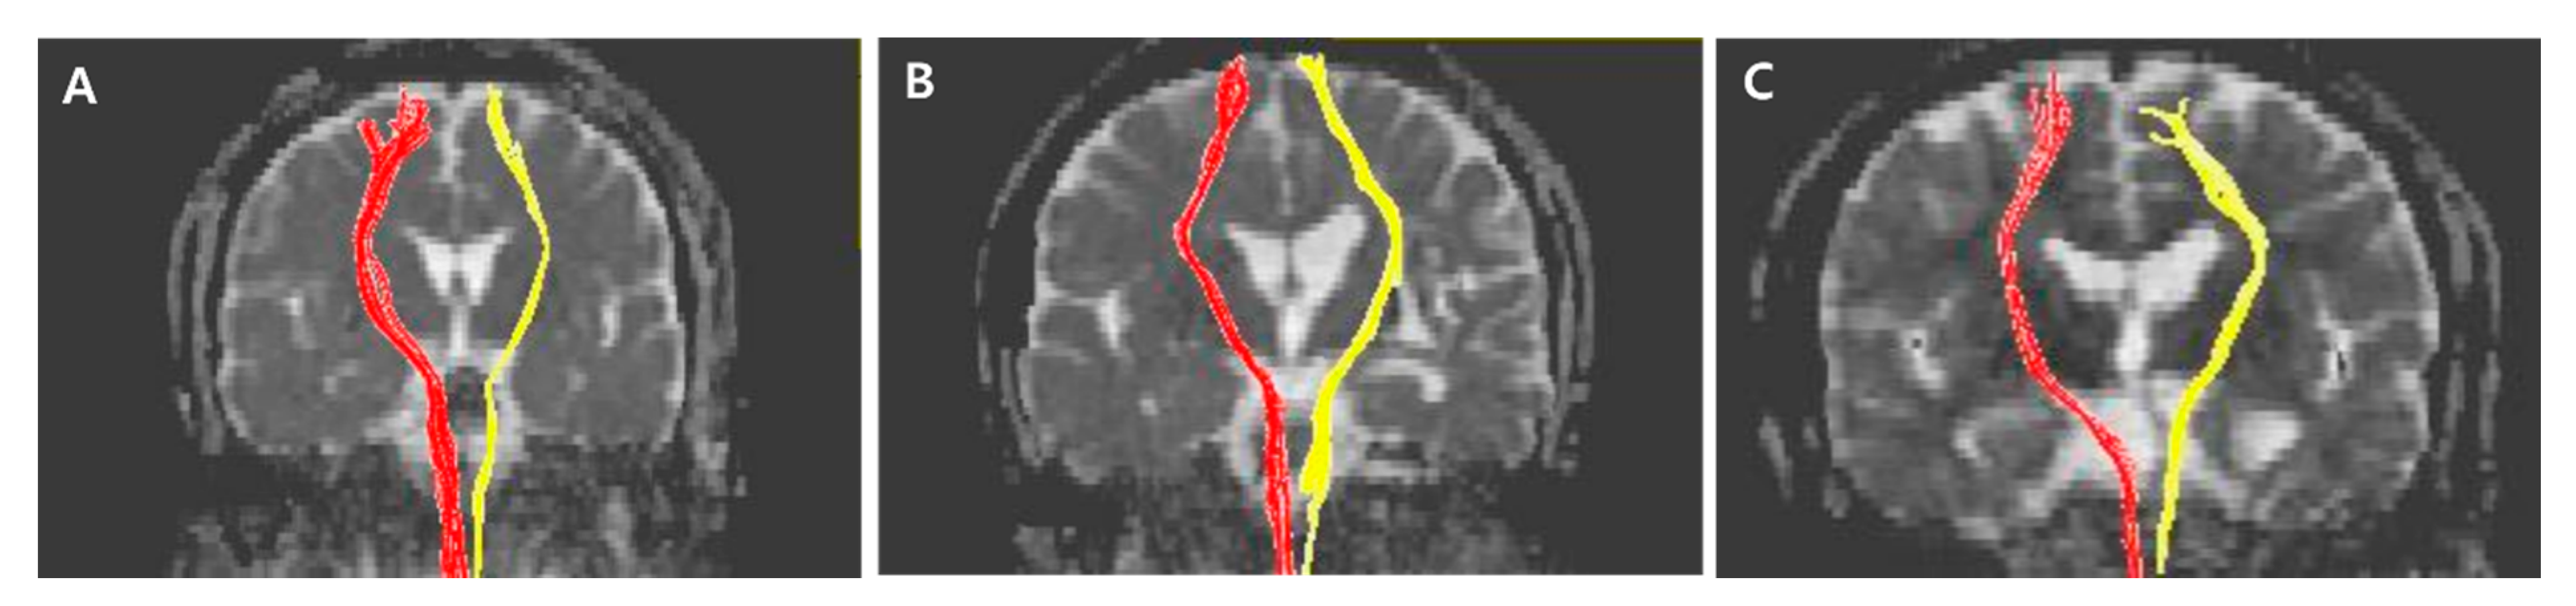

Figure 1. Specific anatomical locations of seed and target regions of interest (ROIs) of anterior thalamic radiation (ATR) and posterior thalamic radiation (PTR) in slice levels in brain MR images. (A) Sagittal view for ROIs, (B) Axial view for ROIs. (a) Target ROI of ATR where the frontal and temporal lobes are separated. Equivalent slice level to (a) in Supplementary Materials Figure S3. (b) Seed ROI of ATR located on the anterior part of the thalamus where the substantia nigra first appears. Equivalent slice level to (b) in Supplementary Materials Figure S3. (c) Seed ROI of PTR located on the posterior part of the thalamus, where the posterior tip of the putamen lies. Equivalent slice level to (c) in Supplementary Materials Figure S4. (d) Target ROI of PTR located below the parieto-occipital sulcus. Equivalent slice level to (d) in Supplementary Materials Figure S4.